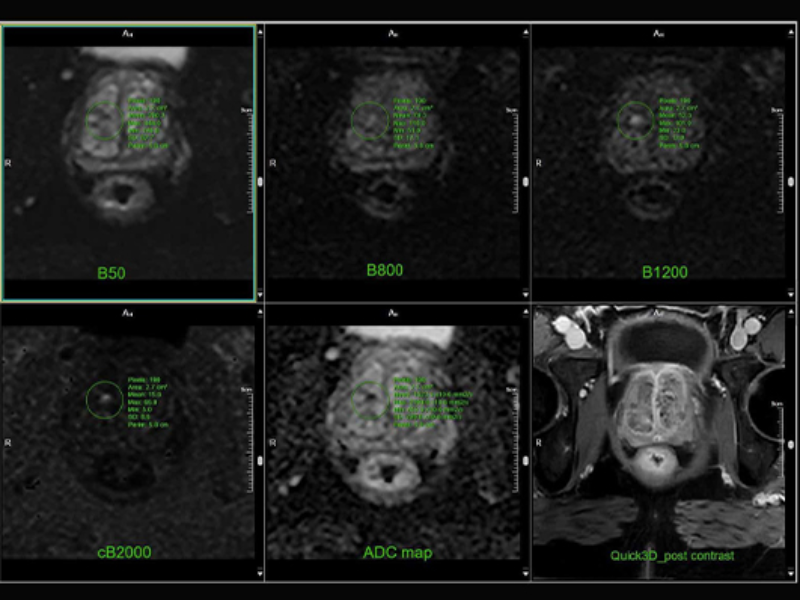

Prostate- DWI with post QUICK 3D

AI-Empowered Compressed Sensing (uAI ACS)

uAI ACS is a novel approach to United Compressed Sensing (uCS) which combines uCS and k-space deep learning to allow for unprecedented acquisition speed image quality . Most multi-contrast exams can be completed in under 100 seconds of active scan time.